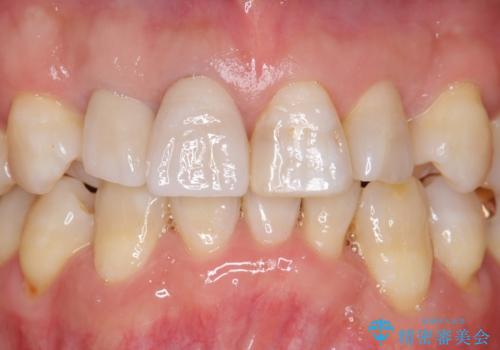

仕上がりに限界はありましたが、比較的短期間で歯並びが整いセラミック治療を行うことができ、患者様に「治療して良かった」とご満足頂けました。

左上1の歯の表面にもともと凹凸とグラデーションがあり、気になるようならセラミックでかぶせるのも一つだと提案しましたがご希望されなかったため、その表面性状を再現して右上1のセラミッククラウンを作製しています。

~被せ物の種類~

右上21:ジルコニアクラウン スペシャル

左上6:ジルコニアクラウン スタンダード

左上7:e-max press セラミックインレー